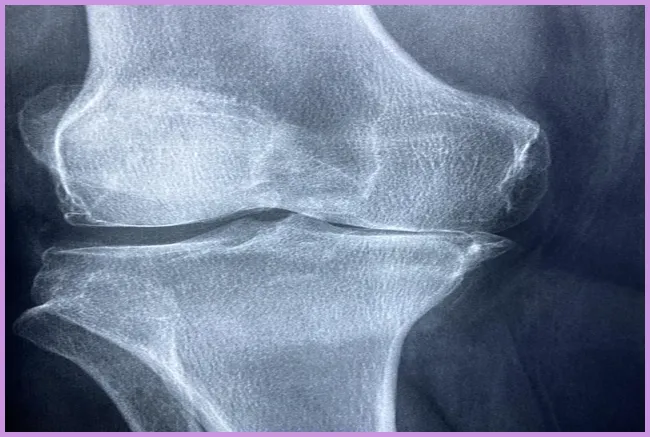

관절염 진단은 나이와 성별, 가족력 등의 다양한 요소를 고려하여 이루어집니다. 의사는 통증이 발생하는 관절을 검사하며, 필요한 경우 X선 촬영이나 혈액 검사를 통해 확실한 진단을 내릴 수 있습니다. 관절염 치료법으로는 비스테로이드 항염증제(NSAIDs)나 스테로이드 주사와 같은 약물치료가 있습니다.